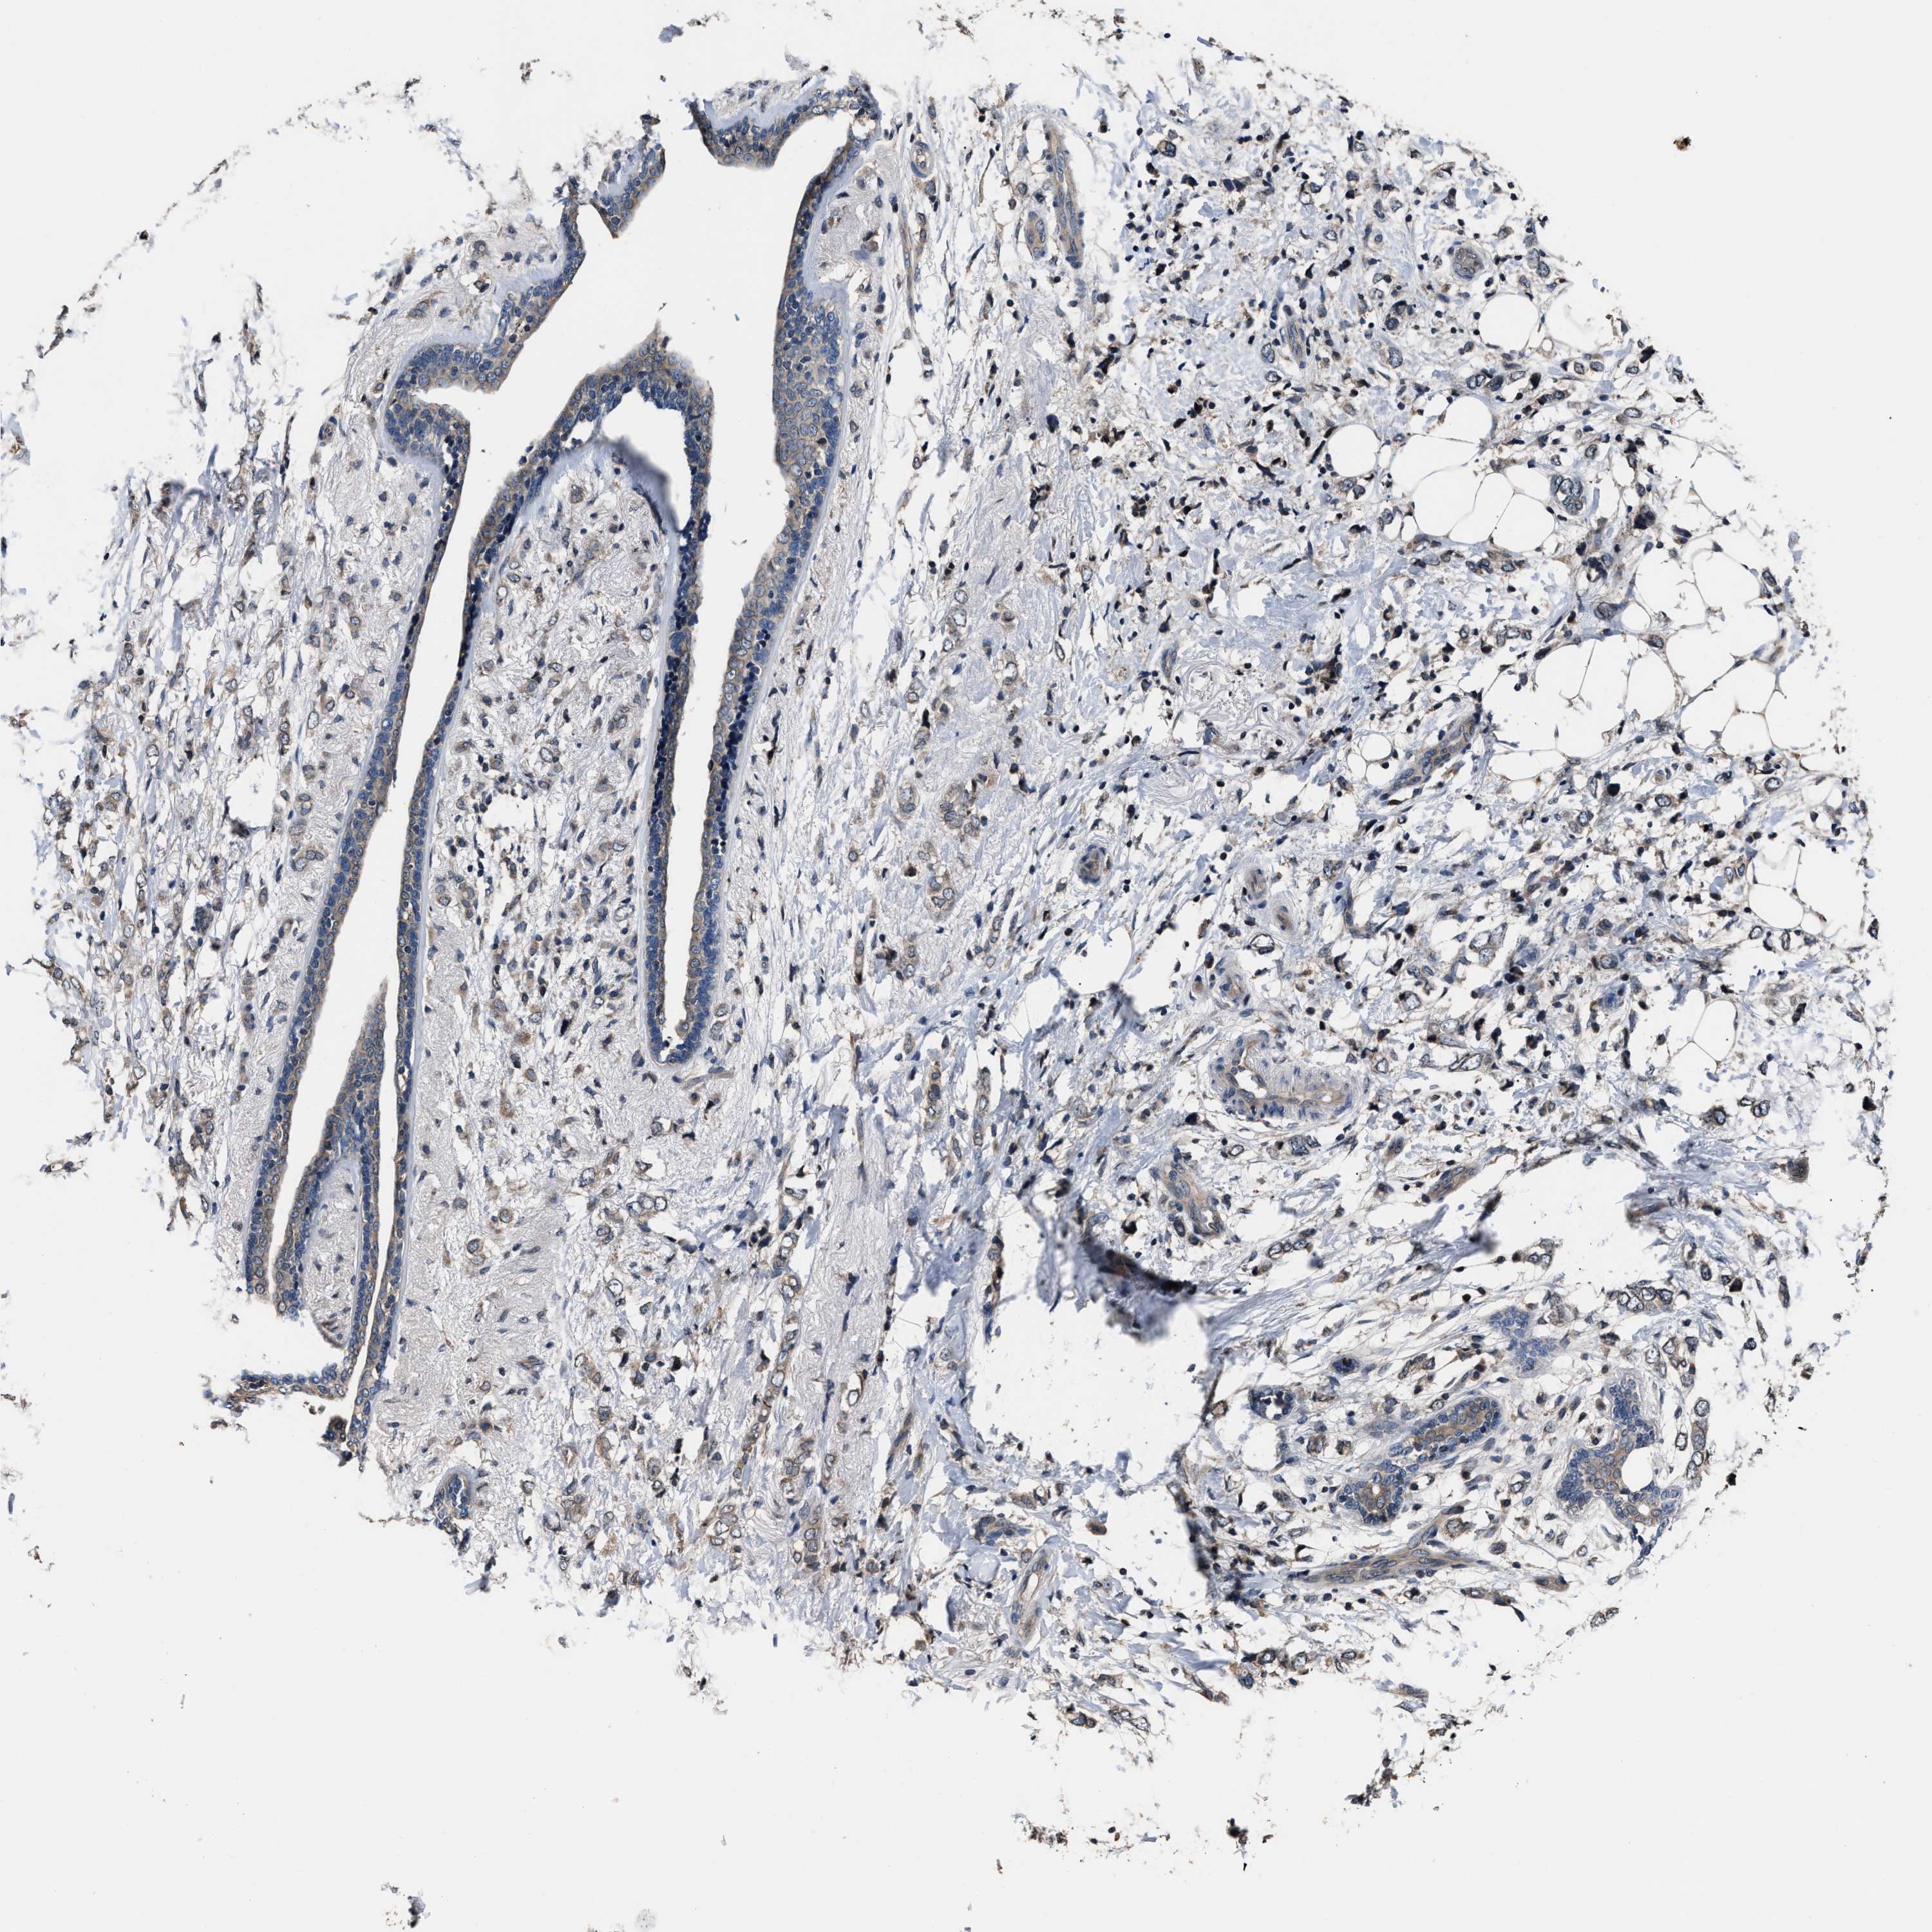

CANCER BREAST CANCER Show tissue menu

BRCA TCGA BRCA VALIDATION PROTEIN EXPRESSION